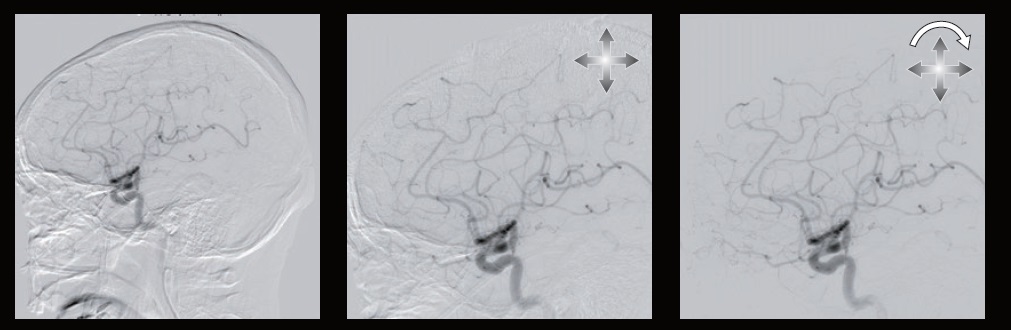

Нейрохірургія

Технологія детектору високої роздільної здатності

Новий, технологічно вдосконалений детектор високої чіткості Canon Medical покращує візуалізацію та збільшує просторову роздільну здатність, щоб під час інтервенційних процедур працювати максимально безпечно та інформативно.

Унікальний гібридний 12-дюймовий (30 см) розмір плоского детектора Canon Medical забезпечує просторову роздільну здатність до 2,5 разів більше. Такі режими збільшення як 3 дюйми (8 см), 2,3 дюйми (4,5 см) та 1,5 дюйми (4 см) тепер можна отримати із неймовірно хорошою роздільною здатністю зображення.

Об'єктивно завдяки більшій роздільній здатності в режимі Hi-Def зображення виходять більш чіткими та якіснішими, ніж зображення в режимі FPD.

Технічно: за першої ж необхідності збільшення з високою роздільною здатністю:

• Стандартні поля зору (FOV) + нові додаткові з Hi-Def;

• Збільшення незалежно на фронтальному та латеральному детекторі;

• Корпус детектора такого ж компактного розміру, як і раніше.

• Робочий процес: повна інтеграція

• Немає затримки в часі при переключенні між режимами;

• Просте використання – без необхідності призвичаюватися.

Автоматичний зсув пікселя

Автоматичне виправлення зсуву положення маски зображення, що був спричинений рухом тіла під час DSA або 2D roadmap. Автоматичний зсув пікселів в режимі реального часу автоматично коригує положення зсуву.

Ця функція автоматично активується після отримання зображення. Для застосування цієї обробки не потрібні дії оператора.